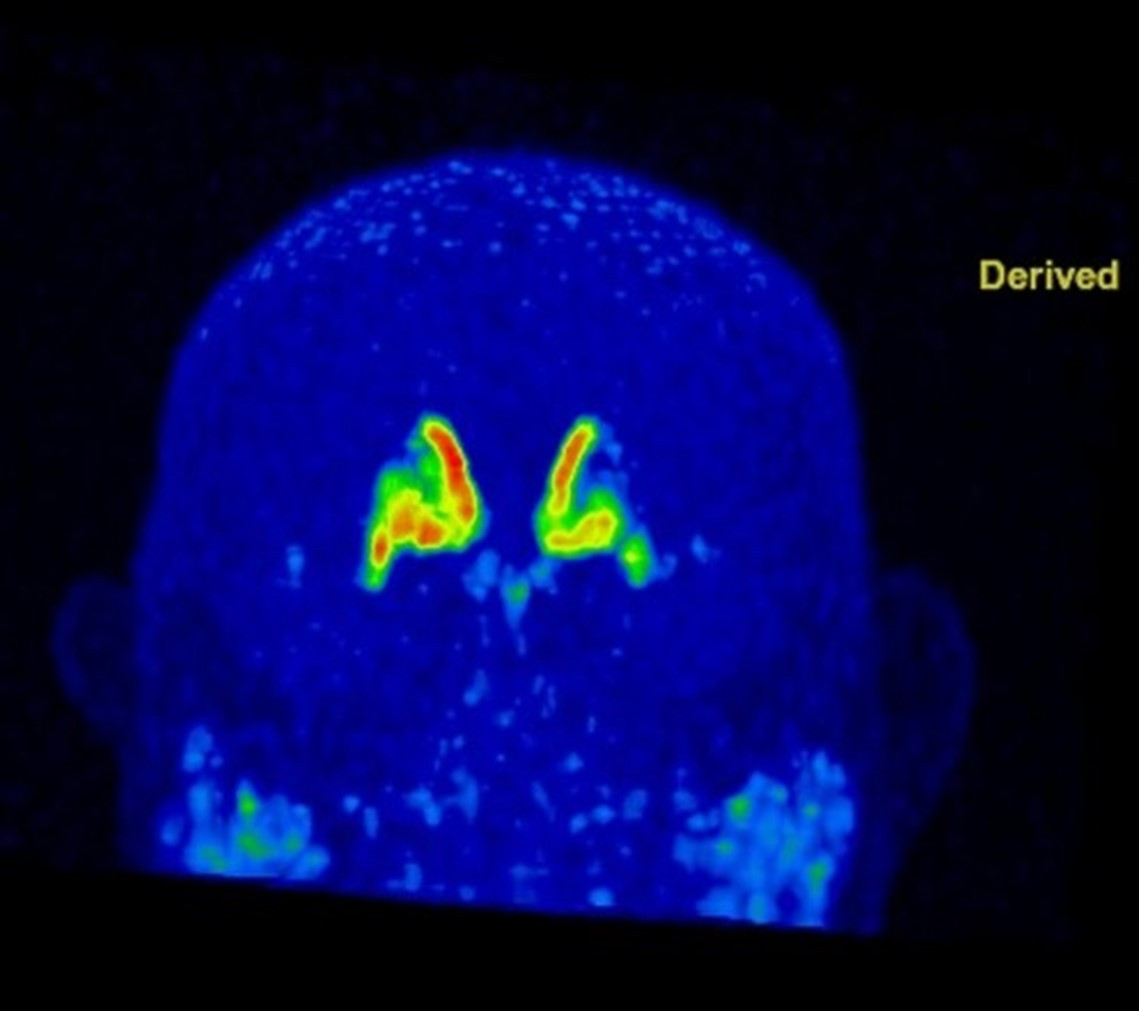

그림3.jpg 촬영 일시: 2025.05.23

<Fig 1. 뇌 PET-CT>

뇌 MRI, 척추 MRI 등 다양한 검사 결과,

결국 제가 각종 파킨슨병 검사를 통해

증명해낸 것은 그분이 바로 <파킨슨병>이라는

사실이었습니다.